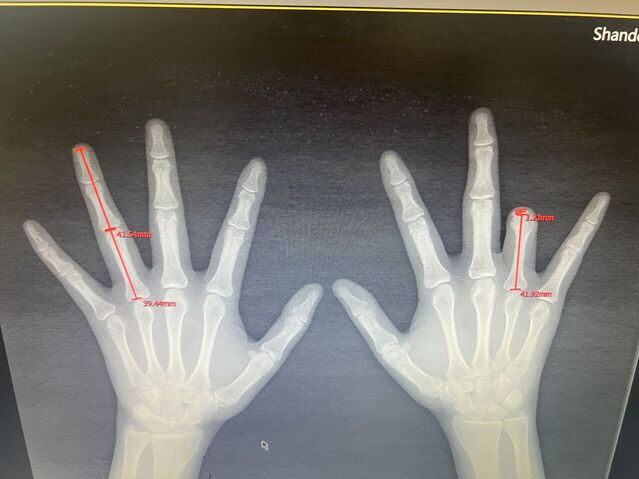

昨天的手术。

微信图片_20231008195909.jpg 微信图片_20231008195912.jpg 微信图片_20231008195906.jpg 微信图片_20231008195903.jpg 微信图片_20231008195829.jpg 微信图片_20231008195839.jpg 微信图片_20231008195836.jpg 微信图片_20231008195945.jpg 微信图片_20231008195939.jpg